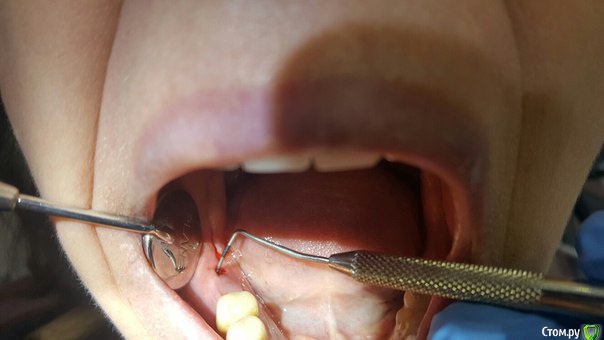

Малик Опубликовано 18 мая, 2016 Поделиться Опубликовано 18 мая, 2016 (изменено) Ровно 3 месяца назад произведена установка имплантата 4.6 с НКР. Заживление первичным натяжением, на момент снятия швов все идеально (К сожалению, нет фоток, не обзавелся еще фотоаппаратом). 2 дня назад позвонила пациентка и сказала, что прям по вершине гребня появилось какое-то образование мягкой консистенции, была назначена на сегодня. Позвонила вчера вечером с жалобой, что данное образование лопнуло, и появилась сукровица. На осмотре определяется свищ по вершине гребня и язычно.Посоветуйте какую тактику предпринять? Раскрыть и поставить формик? И у кого какие мнения по поводу причины этого всего? кт с имплантатом было сделано сегодняP.S. извиняюсь за очень низкое качество фотографий. Изменено 18 мая, 2016 пользователем Малик Ссылка на комментарий